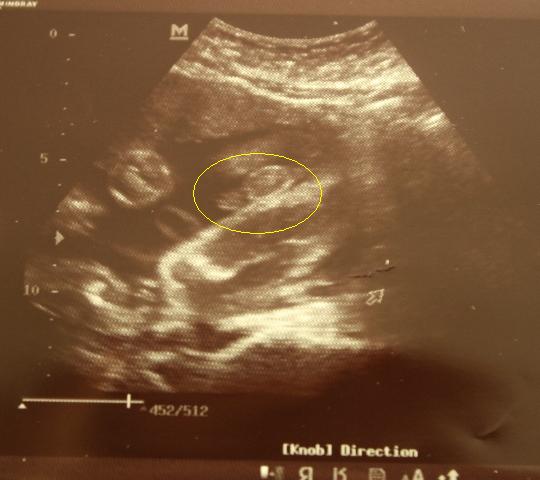

Mam pytanko, która z mam miała dać fotkę "ptaszka" swojego synusia, bo nie mogę się doczekać ( chce porównać z moim" :-)Cały czas mam lęki żeby nie odleciał.